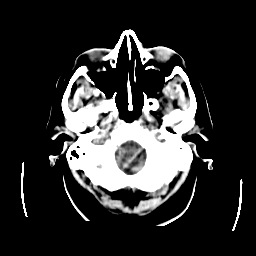

CT Study #2 -- Slice #3